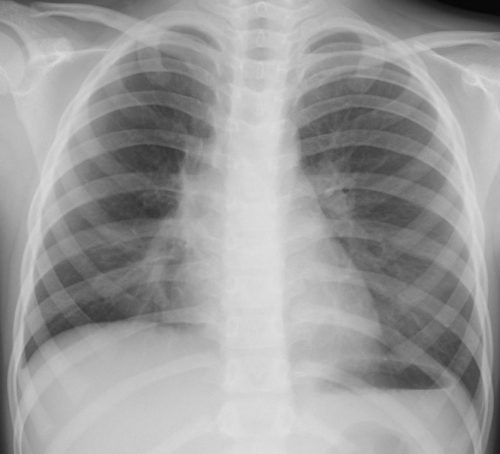

外来でみるクラミジア肺炎

【クラミジア肺炎】